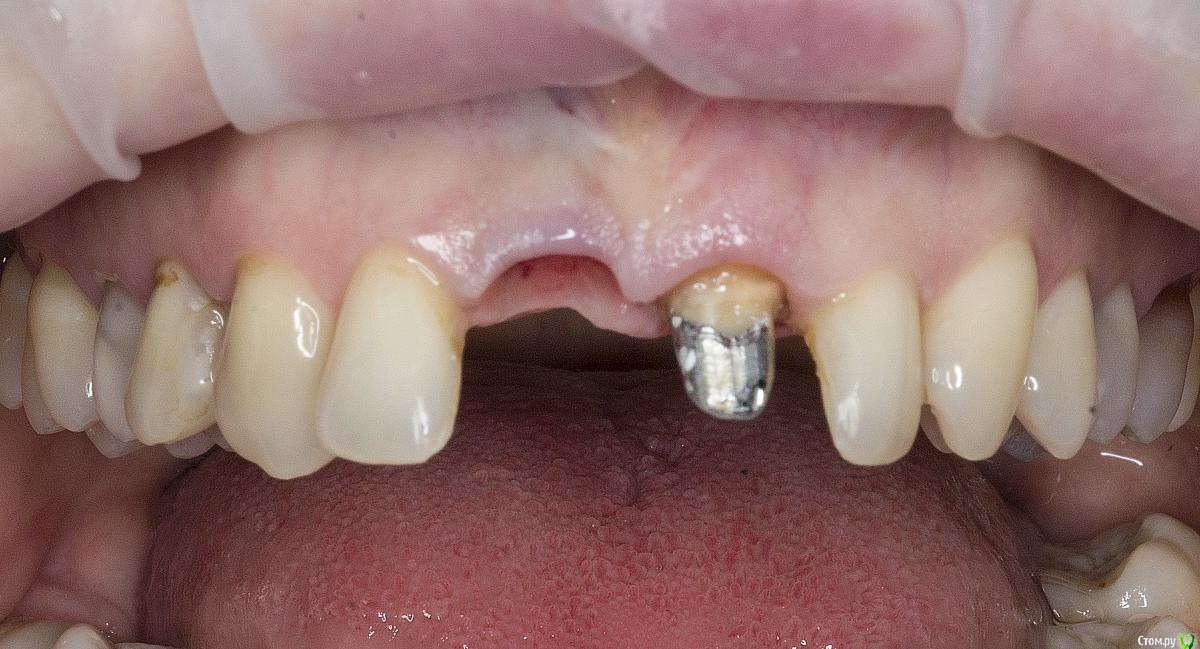

Александр07 Опубликовано 2 мая, 2020 Автор Поделиться Опубликовано 2 мая, 2020 нужна другая форма коронок, может и пластика не потребуетсяОртопед говорит сделал что мог, если отдавить больше десну может и подтянется но объём не мешало бы добавить скорее всего Ссылка на комментарий

Дмитрий М Опубликовано 2 мая, 2020 Поделиться Опубликовано 2 мая, 2020 отдавить больше давить нельзя, наращивать ))) Ссылка на комментарий

Irouil Опубликовано 2 мая, 2020 Поделиться Опубликовано 2 мая, 2020 Я тоже не вижу, что тут еще давить. У коронки плохой контур в пришеечной части, но ближе к платформе винта коронка должна быть тоньше с таким рентгеном, значит там поддержка тканей еще уменьшится. Судя по оклюзионному снимку в оро-вестибулярном направлении коронке не хватает объёма, зенит тоже апикальнее необходимого. Надо разобраться с соседней 1-кой, если замена там коронки - вариант, то можно рассмотреть апикализацию зенита на зубе на 1 мм в итоге. Но, имхо, без хирургии тут не выйдет ничего Ссылка на комментарий

Александр07 Опубликовано 2 мая, 2020 Автор Поделиться Опубликовано 2 мая, 2020 Я тоже не вижу, что тут еще давить. У коронки плохой контур в пришеечной части, но ближе к платформе винта коронка должна быть тоньше с таким рентгеном, значит там поддержка тканей еще уменьшится.Судя по оклюзионному снимку в оро-вестибулярном направлении коронке не хватает объёма, зенит тоже апикальнее необходимого. Надо разобраться с соседней 1-кой, если замена там коронки - вариант, то можно рассмотреть апикализацию зенита на зубе на 1 мм в итоге.Но, имхо, без хирургии тут не выйдет ничего[/quote Да, коронку будут менять на 2.1, и Зенит думаю на 2.1 тоже сместят, правда на 1.1 если сделать выпуклей профиль как полагается скорее всего там ещё зенит выше уйдёт Тогда если с хирургией работать советуете сразу сделать профиль как полагается на 1.1 , сместить Зенит на 2.1, контакт протяженней между 1.1-2.1, и ждать результата , правильно понял ? Ссылка на комментарий

krokomot Опубликовано 2 мая, 2020 Поделиться Опубликовано 2 мая, 2020 Очень важен профиль коронки с вестибулярной стороны, обязательно должен быть нависающий над десной край, который убережет десну от травмы при откусывании, это залог долгосрочного результата. Ссылка на комментарий

Irouil Опубликовано 2 мая, 2020 Поделиться Опубликовано 2 мая, 2020 (изменено) Я тоже не вижу, что тут еще давить. У коронки плохой контур в пришеечной части, но ближе к платформе винта коронка должна быть тоньше с таким рентгеном, значит там поддержка тканей еще уменьшится.Судя по оклюзионному снимку в оро-вестибулярном направлении коронке не хватает объёма, зенит тоже апикальнее необходимого. Надо разобраться с соседней 1-кой, если замена там коронки - вариант, то можно рассмотреть апикализацию зенита на зубе на 1 мм в итоге.Но, имхо, без хирургии тут не выйдет ничегоДа, коронку будут менять на 2.1, и Зенит думаю на 2.1 тоже сместят, правда на 1.1 если сделать выпуклей профиль как полагается скорее всего там ещё зенит выше уйдёт Тогда если с хирургией работать советуете сразу сделать профиль как полагается на 1.1 , сместить Зенит на 2.1, контакт протяженней между 1.1-2.1, и ждать результата , правильно понял ?На мой взгляд, надо начать со снятия коронок, изготовления временной на 2.1, модификации временной на имплантате в сторону истончения поддесневой части, потом хирургия с аугментацией в области 1.1, времяхи на место. 3 месяца на подрасти и подсозреть. Дальше меняем контуры времяхи на винте на правильные (повторение контура зуба до зенита и на 1-1.5 мм апикальнее, далее резкое сужение к тибейсу), ждем еще пару недель. На оставшуюся разницу планируем редукционную хирургию на 2.1 или повторяем уже только вестибулярную аугментацию у 1.1 Изменено 2 мая, 2020 пользователем Irouil 1 Ссылка на комментарий